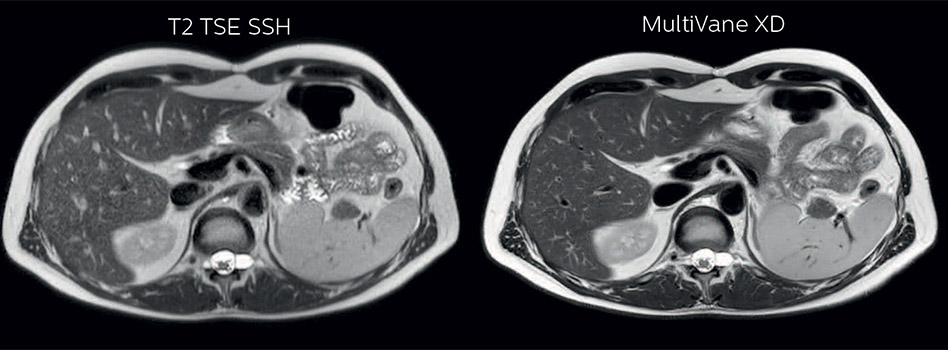

In this example the image quality of the MultiVane XD images is evidently better than in the images without MultiVane XD. Ingenia 1.5T with dS Torso coil solution.

Dr. Baumann then implemented MultiVane XD for motion correction. It uses an extended reconstruction algorithm for imaging that is virtually motion free. “With MultiVane XD we get excellent motion-corrected images with high spatial resolution. We typically first optimize our scan for high image quality, and when satisfied with that, we try to reduce the scan time. So, we combined MultiVane XD with dS SENSE, which allows us to shorten the scan time,” he explains. “The performance of MultiVane XD in liver imaging is outstanding. MultiVane XD with dS SENSE is a powerful development in improving liver image quality.” “As we use breathhold imaging for T2-weighted liver scans, we depend on the patient’s ability to cooperate with the exam. This can present a real challenge when we are looking for small lesions, such as in our oncological patients. However, with MultiVane XD motion correction, we get excellent images. This is important for our surgeons, because they want to know exactly where the lesions are.”